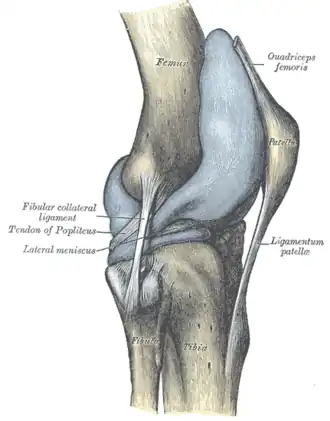

O joelho ainda possui ligamentos que estabilizam a articulação, auxiliados pelos meniscos (interno ou medial e externo ou lateral), que estabilizam o joelho, e amortecem os impactos sobre as cartilagens.

Ligamentos

NomeCápsulaOrigemInserçãoDescrição

ligamento colateral medial ou ligamento colateral tibial (LCM)foraepicôndilo medial do fêmurcondilo tibial medialO Ligamento Colateral Medial protege a parte medial do joelho de ser aberto por uma força aplicada nas laterais do joelho (joelho valgo).

ligamento colateral lateral ou ligamento colateral fibular (LCL)foraepicôndilo lateral do fêmurcabeça da fíbulao Ligamento Colateral Lateral protege as laterais do joelho de uma força dobrante interior (joelho varo).

ligamento poplíteo oblíquoforacôndilo externo do fémurcontinuidade do tendão do semimembranosoExpansão Tendinosa dos musculo semimembranoso. Fortalece a parte de trás da capsula

ligamento poplíteo arqueadoforaárea intercondilar da tíbia côndilo lateral do fêmur a seguir da cabeça fibularConecta para a porção medial da cabeça fibularEste ligamento fortalece o joelho posterolateralmente e quando lesionado está em combinação com uma lesão do tendão PCL e poplítea.